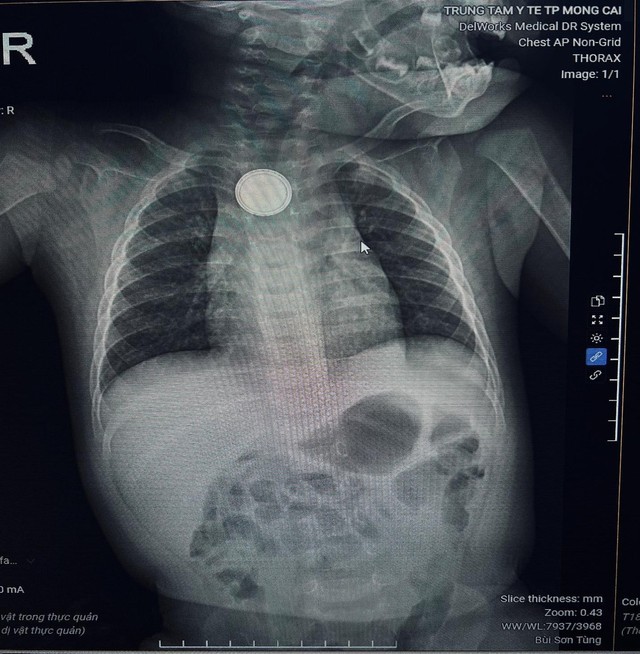

Trung tâm Y tế Móng Cái (Quảng Ninh) vừa tiếp nhận cấp cứu bệnh nhi B.M.K. (11 tháng tuổi) nhập viện trong tình trạng nôn nhiều, quấy khóc dữ dội. Qua thăm khám và chụp X-quang, các bác sĩ phát hiện dị vật kim loại hình tròn mắc kẹt tại thực quản.

Hình ảnh chụp X-quang phát hiện dị vật thực quản/ Ảnh Trung tâm Y tế Móng Cái

Bệnh nhi được chỉ định nội soi cấp cứu, phát hiện dị vật là một viên pin cúc áo. Các bác sĩ nhanh chóng lấy dị vật ra an toàn, tuy nhiên niêm mạc thực quản của trẻ đã bị tổn thương do phản ứng ăn mòn điện - hóa học.